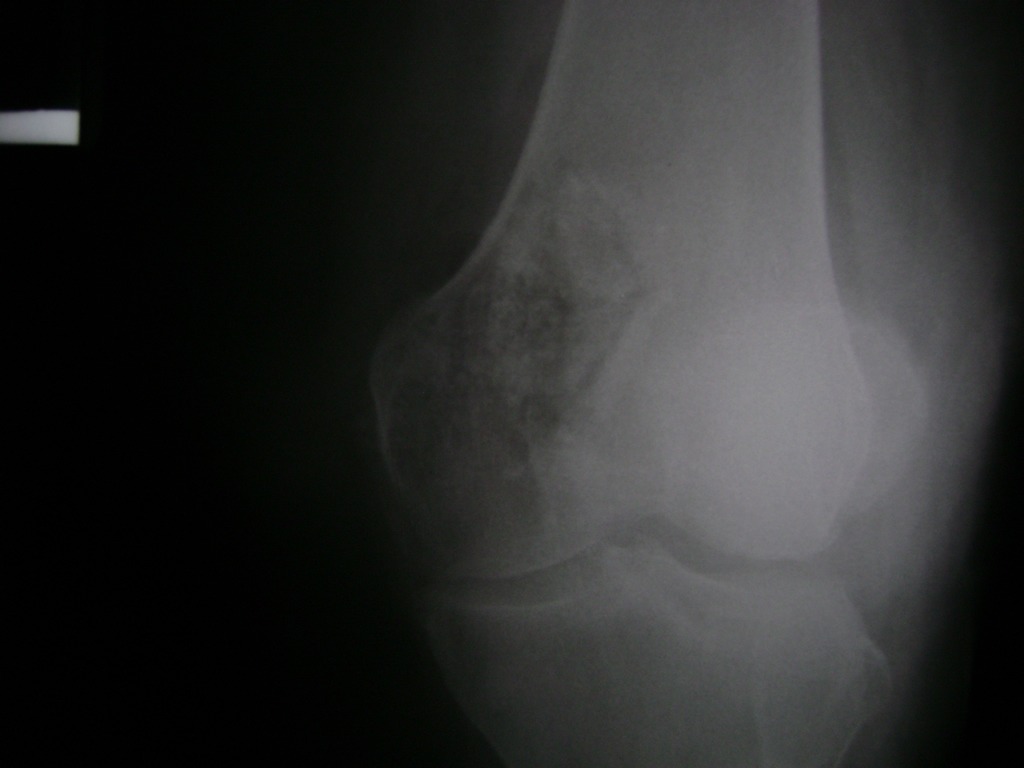

Fémur - Rodilla